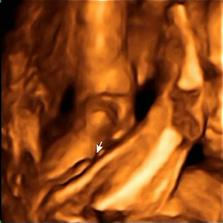

......bude to klučík.....